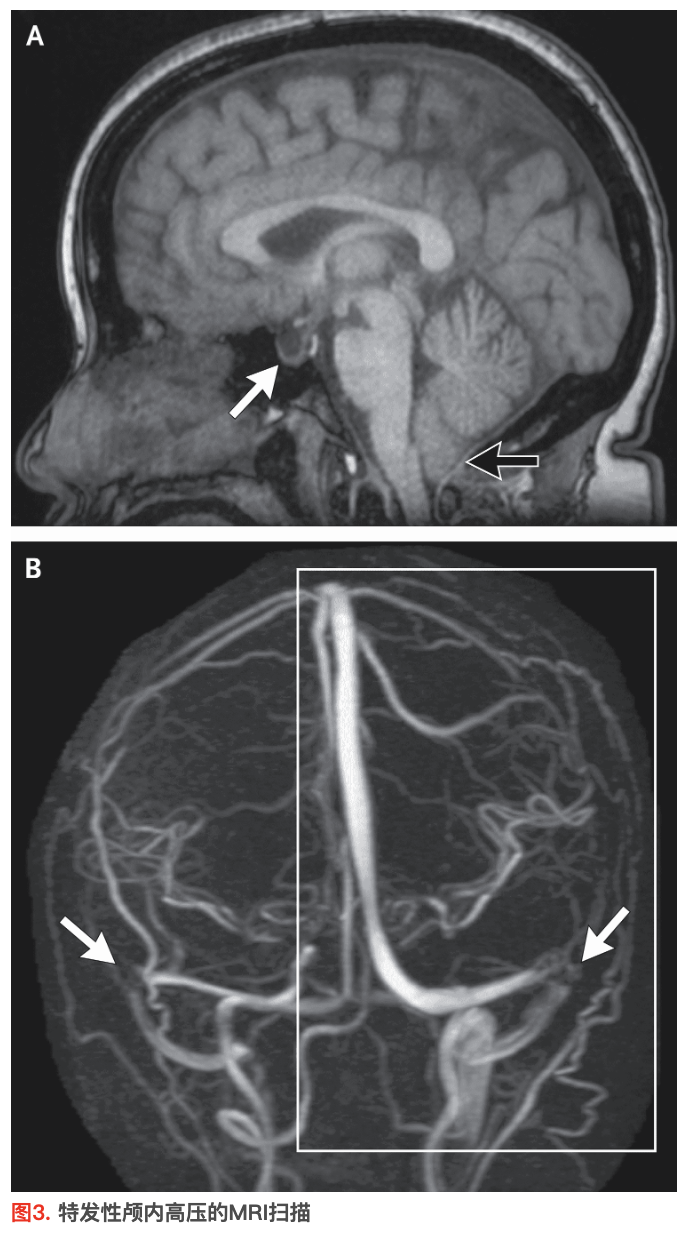

“假性肿瘤”这一名称恰如其分,因为要诊断特发性颅内高压,必须排除颅内肿块。虽然计算机断层扫描(CT)可能足以达到这一目的,但在评估疑似特发性颅内高压导致视盘水肿的患者时,磁共振成像(MRI)优于CT。在注射钆造影剂前后获取序列图像,并实施磁共振静脉造影。ICP升高导致的影像学表现包括视盘向玻璃体腔突出、眼球后部变平、CSF引起视神经鞘扩张、小脑扁桃体向下移位以及部分空蝶鞍。最值得注意的发现是横窦狭窄(图3),因为其对特发性颅内高压病理生理学具有重要意义,在一个病例系列中94%的患者存在该表现25。横窦狭窄通常发生于双侧,或发生于单侧且另一侧横窦发育不全。尽管横窦狭窄并非特异性指标,但在无特发性颅内高压的人群中,该表现发生率低于5%。

图A为图1患者的MRI(非造影矢状位T1加权图像),可见特发性颅内高压典型表现:部分空蝶鞍(白色箭形)和小脑扁桃体向下移位6 mm至枕骨大孔下方(黑色箭形),部分原因可能是腰大池腹腔分流引发的压力梯度。图B为非造影三维相位对比磁共振静脉造影图像,可见双侧远端横窦狭窄(箭形)。矩形框内区域为图5所示静脉系统部分。